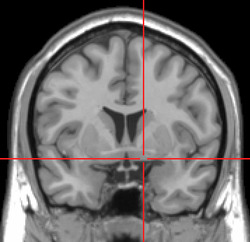

Substantia innominata MRI.PNG

MRI showing a coronal plane of the head with marks showing the location of the substantia innominata, the region in which the nucleus basalis is found.